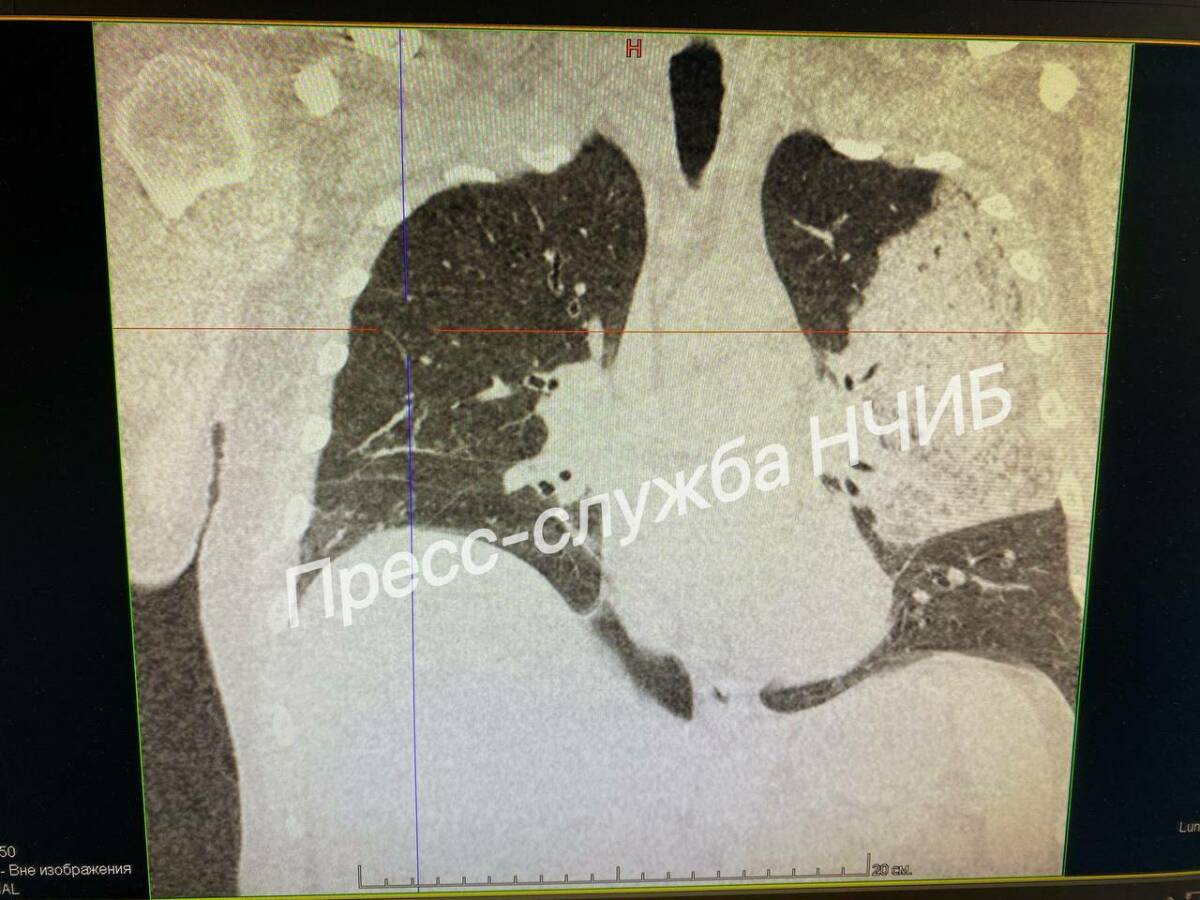

Фото: пресс-служба НЧИБ

51-летний мужчина поступил в больницу в тяжелом состоянии – с высокой температурой, выраженной одышкой и непрекращающимся кашлем. Компьютерная томография выявила обширное поражение легких. Пациента немедленно госпитализировали в отделение реанимации и интенсивной терапии.